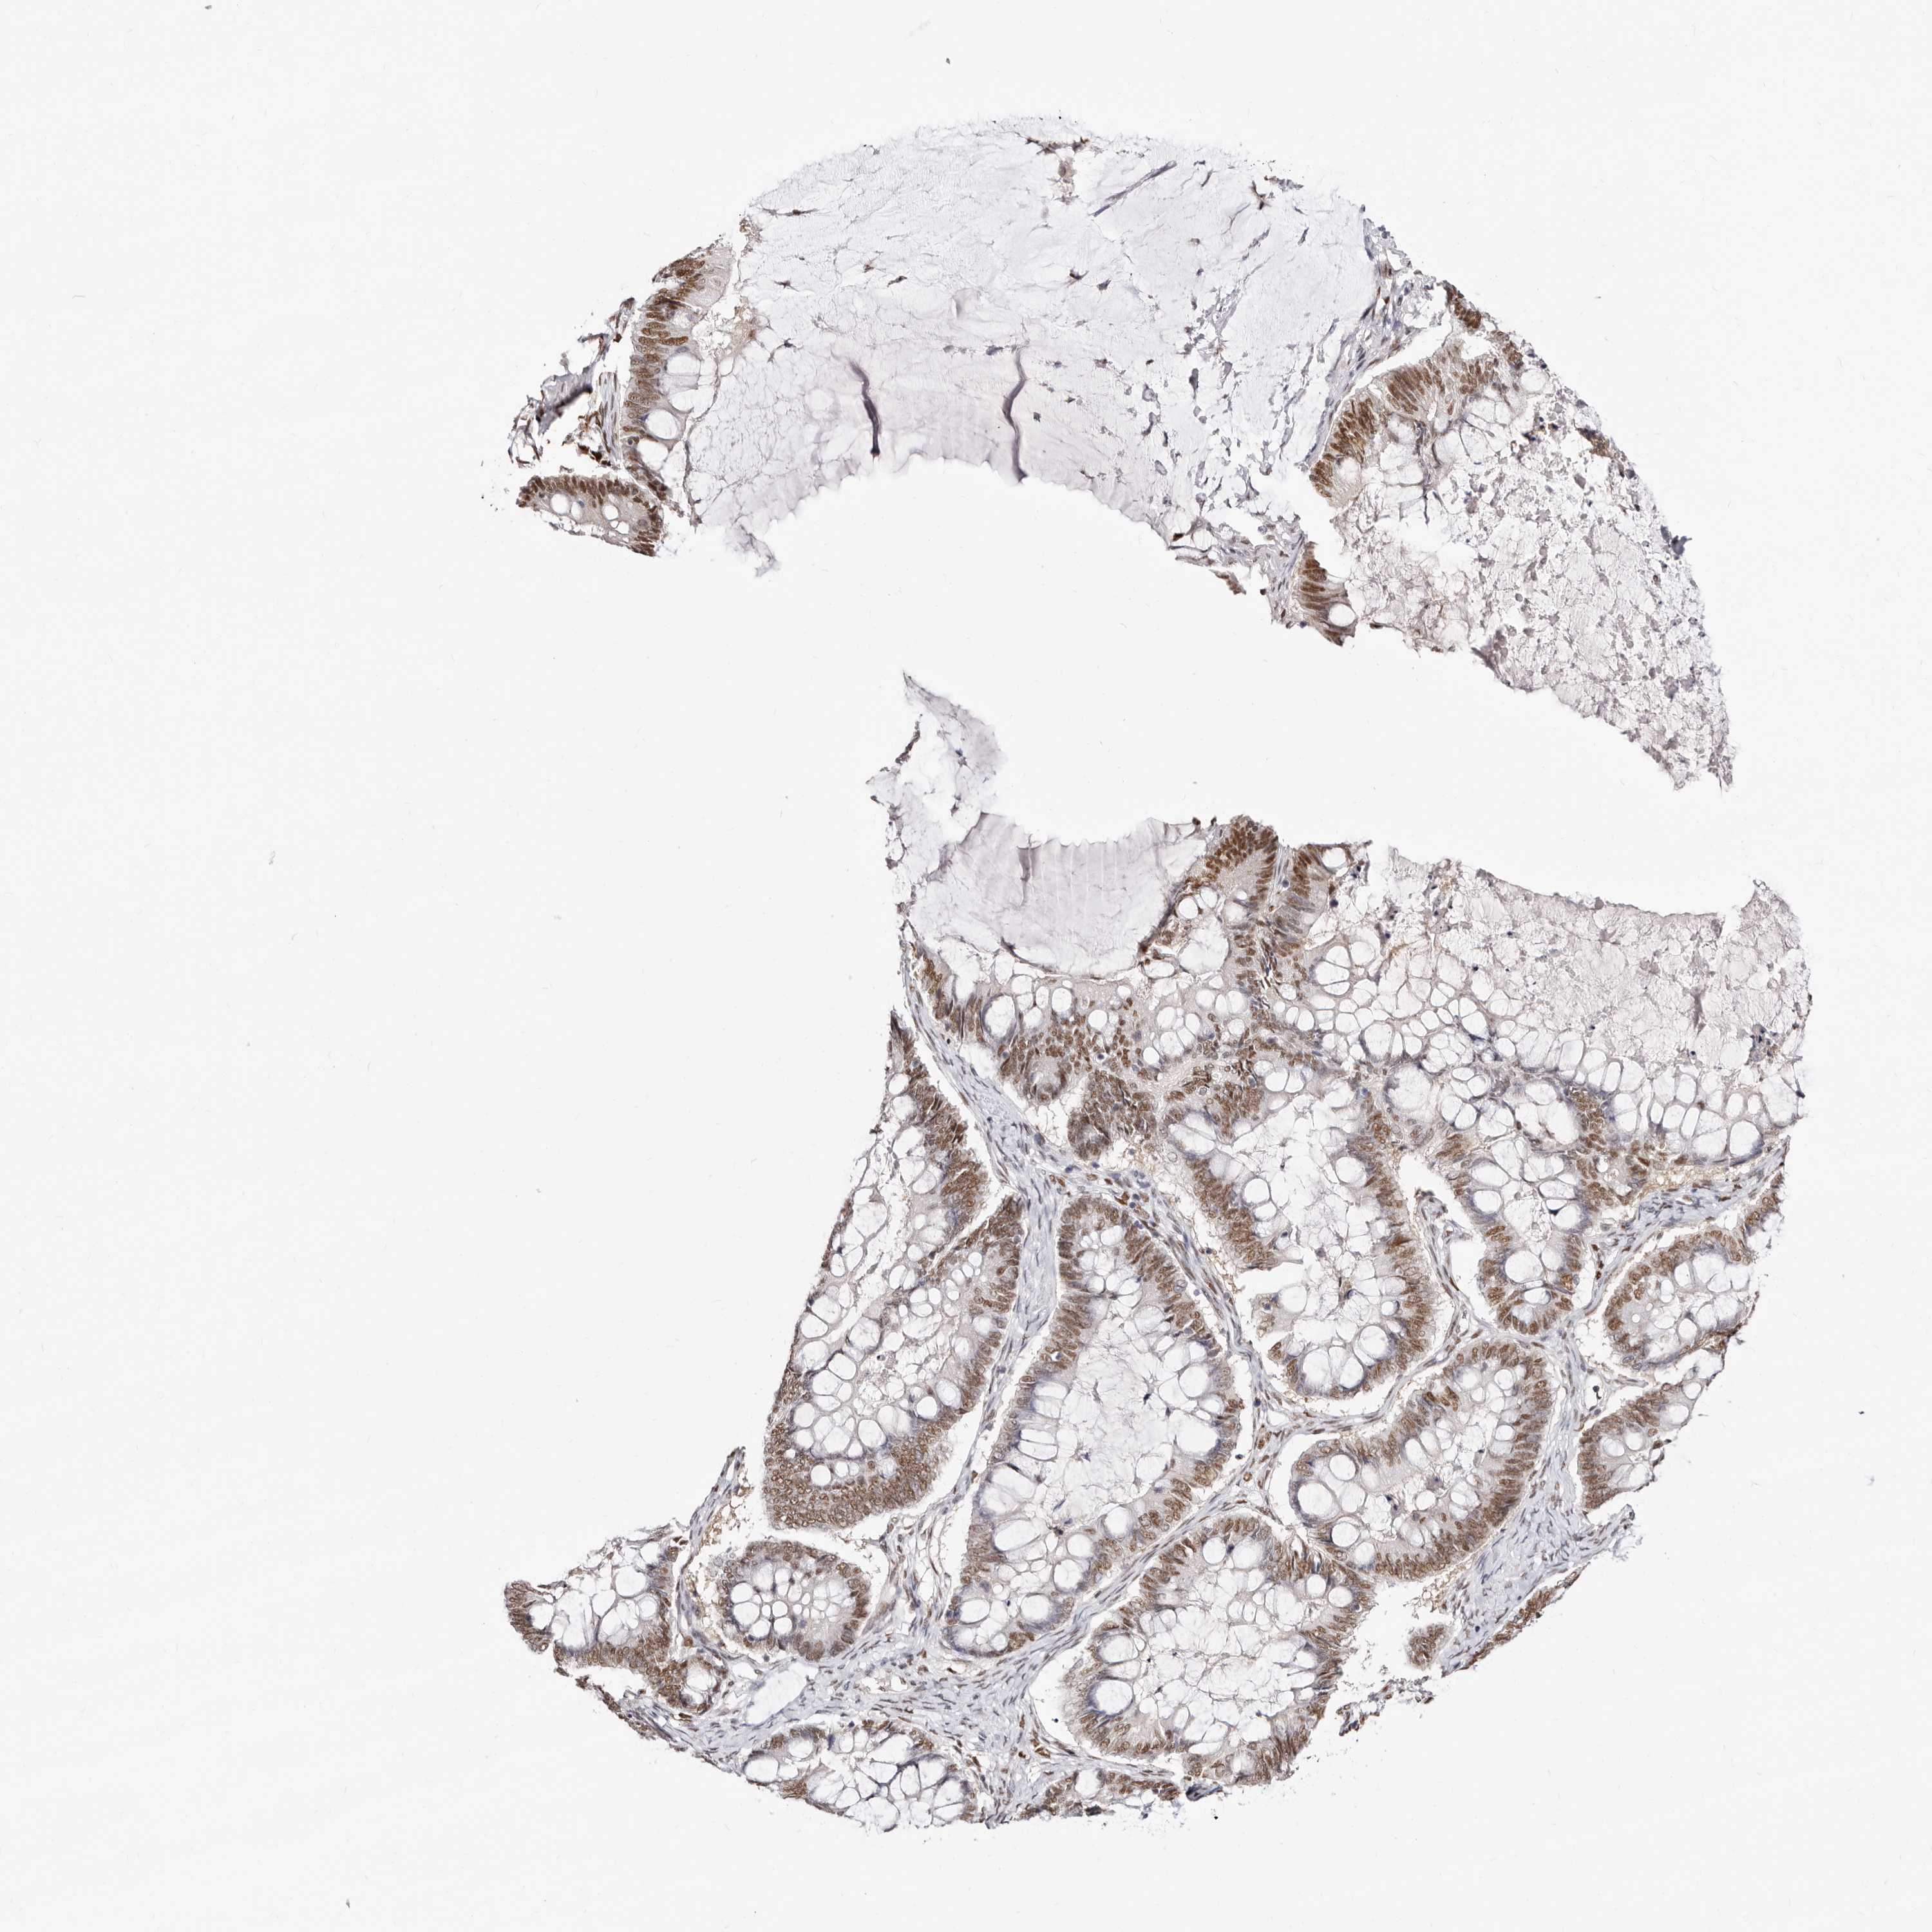

OVARIAN CANCER - Protein expressioni

A mouse-over function shows sample information and annotation data. Click on an image to view it in a full screen mode. Samples can be filtered based on level of antibody staining by selecting one or several of the following categories: high, medium, low and not detected. The assay and annotation is described here.

Note that samples used for immunohistochemistry by the Human Protein Atlas do not correspond to samples in the TCGA dataset.

Antibody stainingi

Antibody staining in the annotated cell types in the current human tissue is reported as not detected, low, medium, or high, based on conventional immunohistochemistry profiling in selected tissues. This score is based on the combination of the staining intensity and fraction of stained cells.

Each image is clickable and will lead to virtual microscopy that enables deeper exploration of all samples and also displays staining intensity scores, fraction scores and subcellular localization as well as patient and tissue information for each sample.

Antibody HPA029480

Antibody HPA029481

Cystadenocarcinoma, serous, NOS

Carcinoma, endometroid

Cystadenocarcinoma, mucinous, NOS

Carcinoma, NOS